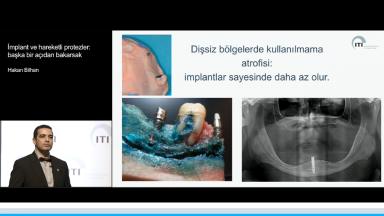

Bölümlü dişsiz hastalarda, protezin hareketini azaltmak, tutuculuğunu artırmak, kalan doğal dişleri korumak ve protezin kapladığı alanı azaltarak, hastaların protezi daha rahat kullanmalarını sağlamanın önemi vurgulanmaktadır. Bu amaçla, olabildiğince az sayıda yerleştirilen implantlar ve konumları hakkında bilgiler verilmektedir. Bu sunumda ayrıca, bu gibi protezlerde kullanılmakta olan tutucular üzerinde de durulduğu gibi, arka bölgeye implant yerleştirilemeyen tam dişsiz vakalarda, sadece ön bölgeye yapılan sabit implant üstü restorasyonlara hassas tutucularla bağlanan bölümlü protezler konusunda da bilgiler verilmektedir.

- İmplant destekli bölümlü protezlerin sağlayabileceği yararlar